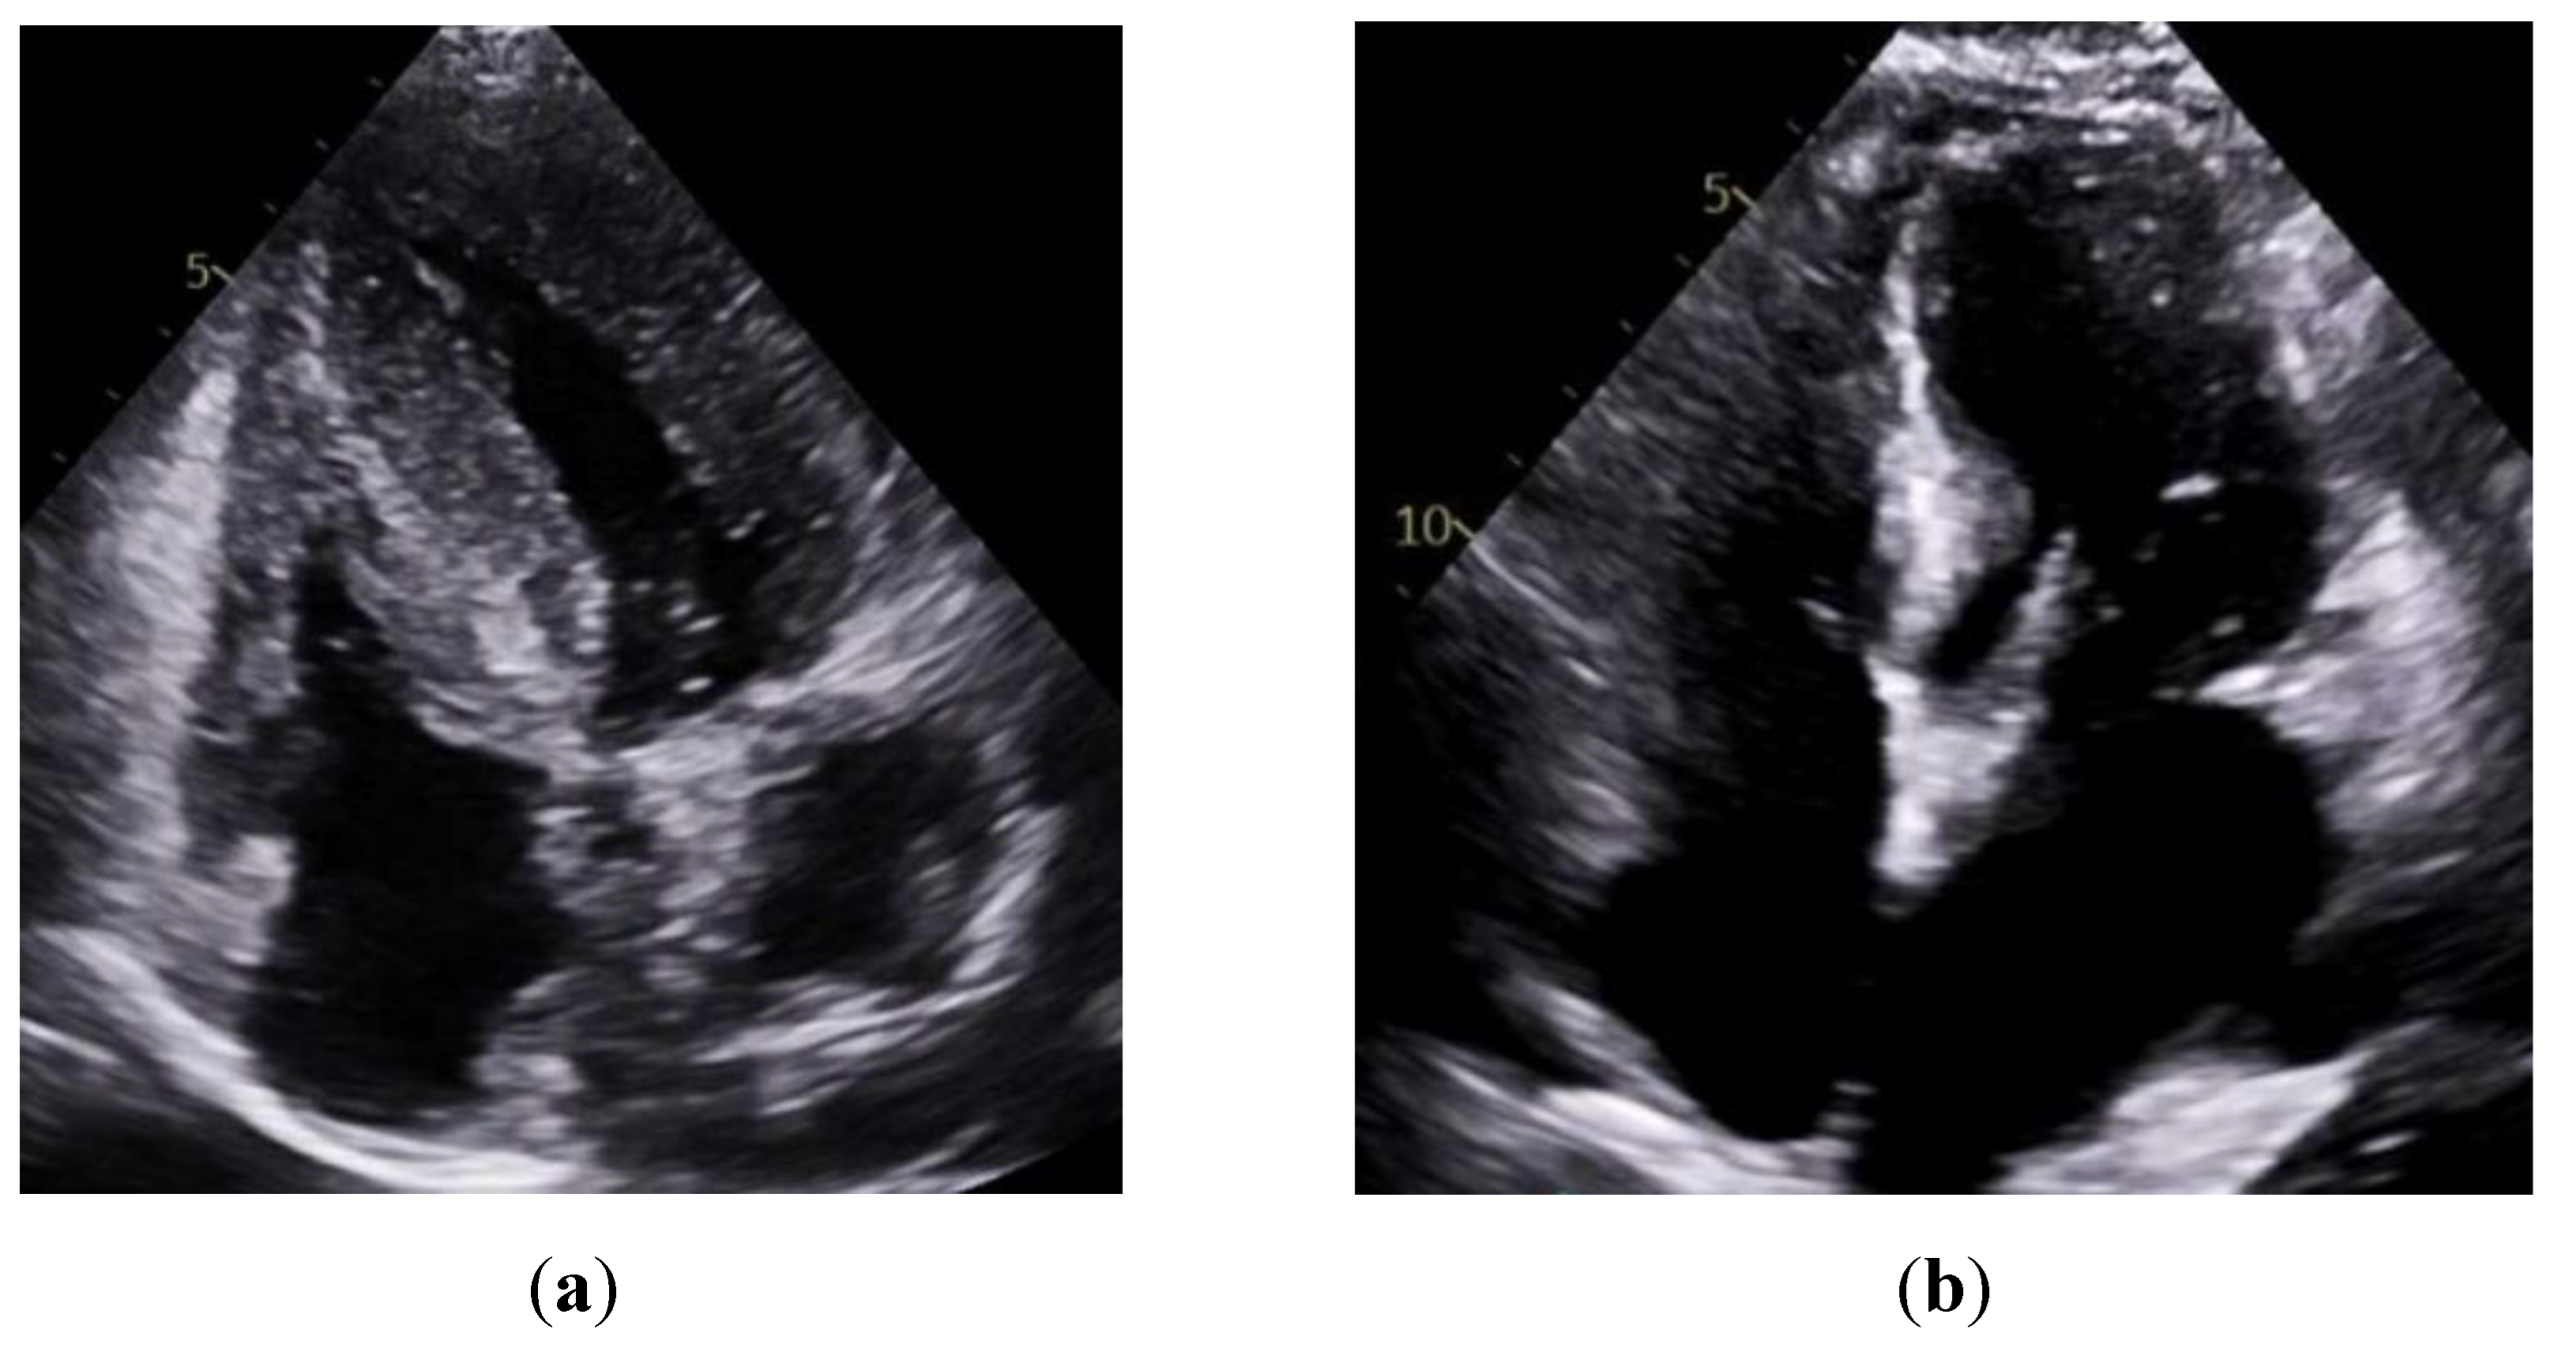

| TTE | EF | 48 ± 15 | 49 ± 14 | 0.70 |

| IVSd | 1.57 ± 0.35 | 1.10 ± 0.25 | 0.01 | |

| LVPWd | 1.45 ± 0.34 | 1.04 ± 0.18 | 0.01 | |